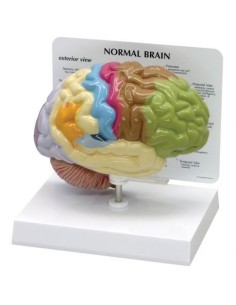

Scopri il Mondo dell’Anatomia con Modelli anatomici di Precisione

Modelli Anatomici Dettagliati per Ogni Necessità

Dal cranio in 22 parti con incastri magnetici ai modelli di colonna vertebrale, da quelli di articolazioni a quelli di cuore, ogni pezzo della nostra collezione è progettato per un’immersione totale nello studio dell’anatomia umana. I nostri modelli, realizzati tramite scansioni di ossa vere, garantiscono un’esperienza tattile autentica e una fedeltà di peso quasi identica agli originali.

Strumenti Didattici Innovativi per l’Educazione e la Pratica Medica

Essenziali per studenti e professionisti, i nostri modelli anatomici sono strumenti didattici che permettono di osservare le strutture anatomiche con precisione, eliminando la necessità di dissezioni o studi invasivi. Sono inoltre utili per spiegare ai pazienti le patologie, rendendo la comunicazione più efficace e risparmiando tempo prezioso.